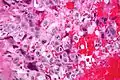

Syncytiotrophoblasts are large multi-nucleated cells with eosinophilic cytoplasm. They often surround the cytotrophoblasts, reminiscent of their normal anatomical relationship in chorionic villi. Cytotrophoblasts are polyhedral, mononuclear cells with hyperchromatic nuclei and a clear or pale cytoplasm. Extensive hemorrhage is a common finding.

High magnification Very high magnification

Very high magnification